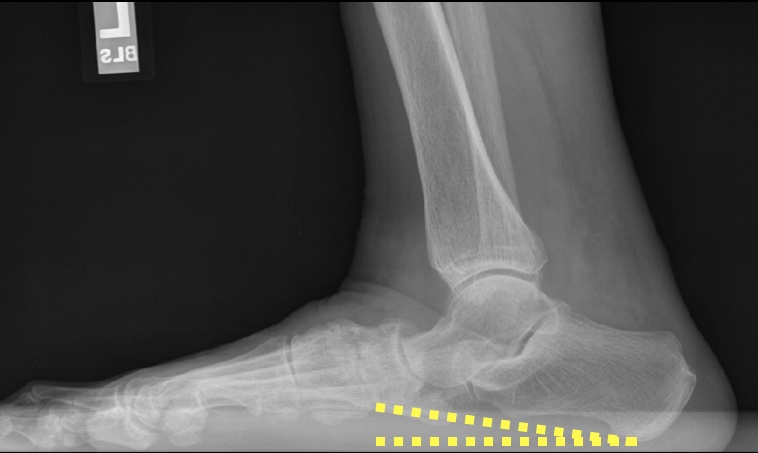

DEFINITION:

angle formed by the horizontal and a line from the base of heel & inferior cortex of calcaneus (figure 1). compare to pes planus (figure 2).